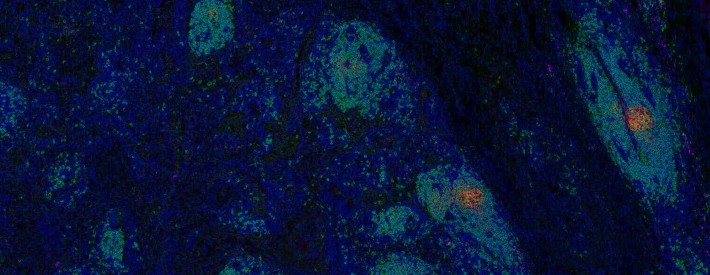

The Cascone Laboratory is focused on identifying immune-mediated mechanisms of tumor response and resistance to immune checkpoint therapies.

The Cascone Laboratory uses information generated from preclinical models of spontaneously metastatic non-small cell lung cancer (NSCLC) and samples derived from patients with operable NSCLC treated with perioperative immune-based therapies to identify determinants of tumor resistance to immune-based therapies, discover predictive biomarkers of therapeutic response in primary resected and metastatic NSCLCs, and discover novel therapeutic targets and strategies that may improve the cure rates of patients with operable non-small cell lung cancer by preventing tumor recurrence, enhancing antitumor immunity and augmenting the efficacy of immunotherapies.